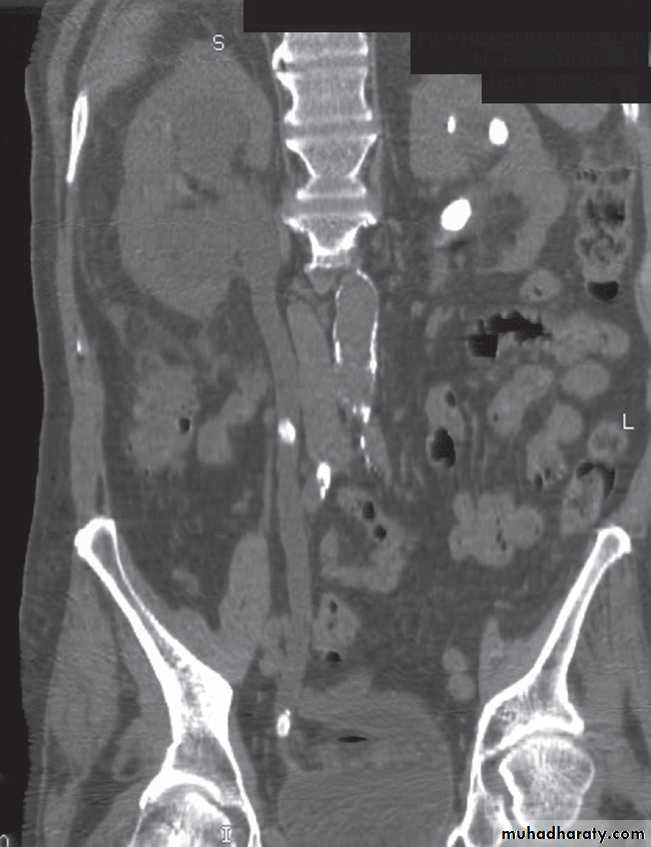

The principal feature of obstruction is dilatation of the pelvicaliceal system and ureter. collecting system is dilated down to the level of the obstructing pathology and demonstrating this level is a prime objective of imaging .Ultrasound and urographic examination play major roles when evaluating urinary tract obstruction, and CT urography has overtaken IVU for the investigation of obstruction .

Ultrasound Dilatation of the pelvicaliceal system ( hydronephrosis ) is demonstrated sonographically as a multiloculate fluid collection in the central echo complex, caused by pooling of urine within the distended pelvis and calices .

Major DDX are multiple renal cysts. With prolonged obstruction, thinning of the cortex due to atrophy will be seen.

Some causes of obstruction are identifiable (e.g. carcinoma of the bladder or a stone at the vesicoureteric junction), it is often not possible to determine the cause of urinary tract obstruction at ultrasound examination.